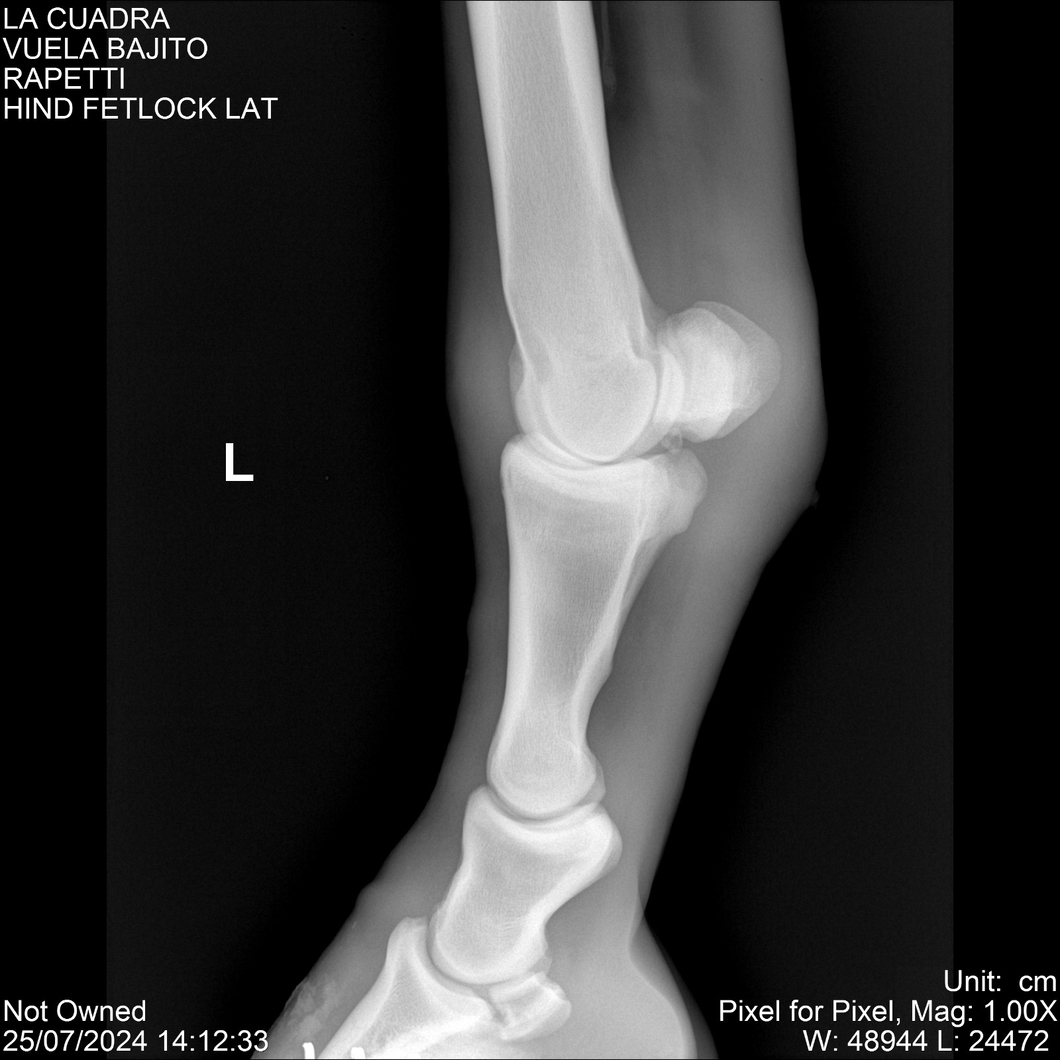

LOTE 16, VUELA BAJITO Lote Anterior Volver al remate Lote Siguiente Ficha Contacto Montevideo - Ficha del Lote Identificador: #284451 Categoría: Yeguarizos Montevideo - 77 Visualizaciones ClicData Contacto Empresa: Abelenda N. R., Walter Hugo Nombre*: Teléfono* : E-mail* : Mensaje Enviar Registrese gratis Este contenido Exclusivo está disponible sólo para usuarios registrados Ingresar